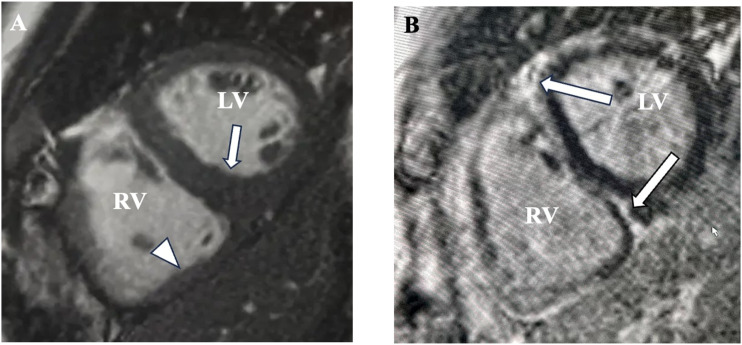

心脏淀粉样变性是一种浸润性心肌病,由异常折叠蛋白沉积在心肌内引起。几种淀粉样蛋白亚型已被证实,诊断支持异常血浆电泳、多模态成像和心内膜肌活检。在此,我们描述了不典型的MRI发现血管变异性心脏淀粉样蛋白支持的组织病理学诊断。血管变异性心脏淀粉样蛋白(淀粉样蛋白沉积于心肌血管而非间质)的知识将使临床医生能够进行适当的诊断和治疗。

Cardiac amyloidosis is an infiltrative cardiomyopathy caused by the deposition of abnormally folded proteins within the myocardium. Several amyloid subtypes have been documented, with diagnosis supported by abnormal serum plasma electrophoresis, multimodality imaging, and endomyocardial biopsy. Herein, we describe the atypical MRI findings of vascular-variant cardiac amyloid supported by histopathological diagnosis. Knowledge of the vascular-variant cardiac amyloid, in which amyloid deposits in the myocardial vasculature rather than the interstitium, will enable clinicians to proceed down appropriate diagnostic and treatment pathways.